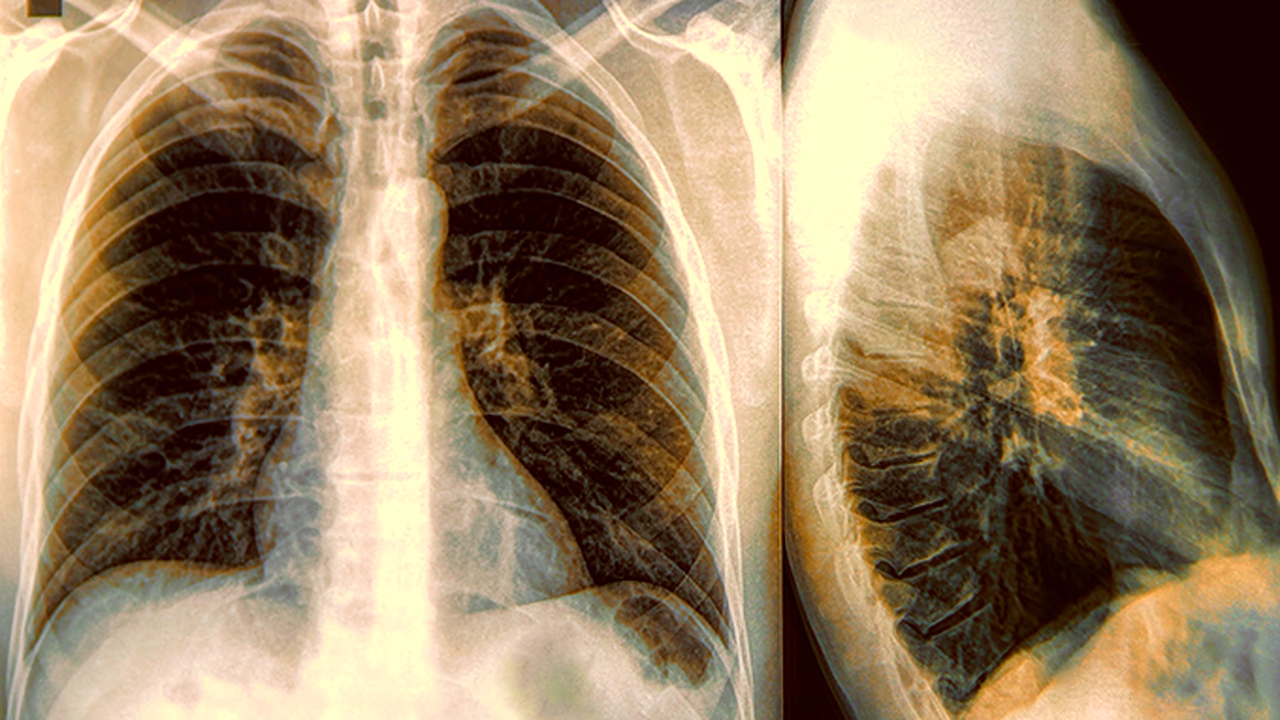

咳嗽有白痰期間應避免進(jìn)食辛辣刺激食物,適量飲用蜂蜜水或羅漢果茶潤喉。每日飲水不少于1500毫升,有助于稀釋痰液。若癥狀持續超過(guò)2周,或出現痰色變黃綠、發(fā)熱、胸痛等情況,需及時(shí)到呼吸內科就診完善胸部X線(xiàn)等檢查。過(guò)敏體質(zhì)人群建議記錄咳嗽發(fā)作時(shí)間與環(huán)境因素關(guān)聯(lián),便于醫生判斷誘因。